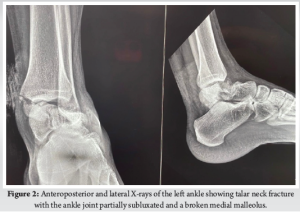

Case Report: We share this unusual case of a Hawkins type-3 talus neck fracture along with a serious Grade 3B medial malleolus fracture and ankle subluxation, which was treated with cleaning the wound, realigning the ankle, and surgery to fix the bones. Post-operatively, the wound was healthy and free of infection. Despite being told to avoid weight-bearing for three months, the patient lost follow-up after a month and started occasional partial weight bearing. During the 10th post-operative week, we found a mild degree of talar neck collapse and Hawkins sign radiologically. The range of motion for the ankle was dorsiflexion of 0–15° and plantar flexion of 0–30°, with minimal swelling and pain on weight bearing.

The combination of talar neck fracture and ankle subluxation, along with ipsilateral medial malleolar fracture, is exceptionally rare. Very few cases have been reported until now [4,5]. Numerous reports have been made of complications, such as osteonecrosis, collapse, malunion, post-traumatic arthritis, and discomfort [3]. The time of definitive fixation depends on multiple factors, including fracture comminution and subtalar dislocation/subluxation [6,7]. Talus fractures that happen with a malleolar fracture have a lower chance of avascular necrosis (AVN) because the ligament-capsule complex between the broken piece and malleolus is still intact, which helps keep the blood supply and soft tissue healthy. In our case, we operated on an emergency basis within 10 h of injury due to associated fracture comminution, open soft tissue injury, and unreduced ankle subluxation to minimize the risk of future avascular necrosis. A retained broken guide wire during medial malleolus fixation was decided not to remove given its harmless intramedullary position and to prevent the further soft tissue damage that will incur during the extraction process that will increase the overall operative time and chances of infection. Although asymptomatic, this intraoperative event underscores the need for caution during hardware placement and raises potential concerns for future procedures. Post-operative x-rays revealed a partial Hawkins sign in the central and medial region of the talar dome, which is reliable evidence of talus vascularity after fracture and suggests that the chances of AVN are unlikely [8,9]. Our case was managed without CT or MRI, which the patient declined given the patient’s poor socio-economic status. While this limited detailed fracture assessment, it emphasizes the role of clinical judgment and standard radiographs in urgent surgical decision-making when advanced imaging is unavailable. The present standard for treating talus neck fractures is to use the anteromedial and anterolateral dual incision techniques [6]. In our case, we used the open medial wound proximally and extended the incision anteromedially and distally. Open fractures, which are frequently accompanied by soft tissue contamination and stripping, were discovered to have a 25% deep infection risk in open talus injuries [10]. The emergency reduction of dislocation, limb elevation, appropriate antibiotic administration, and tension-free suturing of the wound can all help to reduce soft tissue and wound problems, such as skin necrosis, infections, and poor wound healing [6]. Our patient showed no signs of a superficial or deep surgical site infection after surgery. While the single anteromedial approach was effective in our case, further randomised comparative studies with standard dual-incision techniques will be required to study the relative benefits or limitations of this approach. Several studies [6] have found a correlation between poor functional results and increasing injury severity. Although our patient lost contact after a month and began intermittent partial weight-bearing, the patient had better functional results. Talar neck malunion rates can range from 20% to 37%, while talar neck nonunion rates are uncommon (5% each) [7]. On the X-ray taken in the 10th week following surgery, there was no sign of talar neck malunion in our case. Despite instructions for strict non-weight bearing, the patient began early partial weight bearing. This sub-optimal compliance is explained by the poor socioeconomic status, cultural belief, long travel distance from their rural area to the hospital etc. This introduces a variable in outcome interpretation and underscores the importance of understanting the patient’s socio-economic condition. Post-traumatic subtalar arthritis is a typical long-term complication in such cases [7]. Our case requires a long-term follow-up since post-traumatic arthritis progresses over time. Our patient discontinued follow-up after one month, returning only at the 10th week yet presented with good clinical and functional outcome given the complexity of the case presentation. This highlights the challenges of ensuring long-term monitoring in trauma cases, especially in socioeconomically constrained populations.